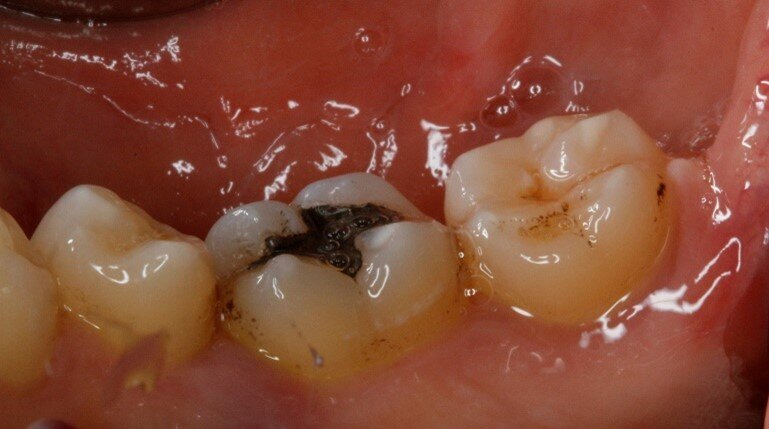

Il secondo paziente è un uomo di anni 55 con anamnesi negativa, che non assume farmaci e non fuma. All’esame obiettivo si notano immediatamente black stains molto evidenti sui versanti vestibolari dei denti posteriori. Si procede con la raccolta della documentazione fotografica, la rilevazione dell’indice di placca attraverso l’utilizzo del rivelatore di placca e la compilazione della cartella parodontale. Dall’analisi dei dati raccolti si deduce che il paziente ha sofferto in passato di parodontite e ha affrontato terapia parodontale non chirurgica per stabilizzare la situazione parodontale. Ad oggi il parodonto è stabile e l’igiene è discreta (IP=30%). Vengono raccolti in una tabella riassuntiva anche i dati relativi alla presenza di black stains. Si prosegue con la motivazione e l’istruzione ad un’accurata igiene orale domiciliare e si sottopone il paziente ad una seduta di igiene orale professionale. Dopo aver effettuato la seduta di igiene professionale si chiede al paziente di cambiare testina allo spazzolino elettrico in uso e di assumere “Lautoselle” una volta al giorno per i tre mesi successivi. Il paziente viene controllato dopo un mese e quindi al termine di questo periodo di assunzione del probiotico, vengono nuovamente scattate delle fotografie e compilata la tabella riassuntiva per monitorare la formazione delle black stains. Nonostante il miglioramento dell’igiene orale domiciliare, visti anche gli impegni personali e lo stile di vita del paziente stesso, si decide di procedere ad un deplaquing con polveri di glicina per mantenere lo stato di salute orale del paziente e di interrompere lo studio.

Durante la prima raccolta dati sono stati rilevati 31 siti totali che presentavano black stains (Tab. 4), 13 siti nel controllo ad un mese dall’inizio dell’assunzione di “Lautoselle” (Tab. 5), infine, 18 siti una volta terminata l’assunzione di “Lautoselle” (Tab. 6); di questi ultimi tutti i siti che presentano black stains sono di primo grado e molto meno evidenti rispetto alla prima raccolta dati. Rispetto al caso precedente i risultati sono stati meno soddisfacenti: i siti che presentano black stains corrispondono al 55,8% rispetto a quelli iniziali già al termine del periodo di assunzione di “Lautoselle”. Va in ogni caso considerato che i pigmenti presenti sono molto evidenti e che, per ammissione del paziente stesso, l’assunzione del probiotico non è stata scrupolosa (Figg. 5a-5c).

Fig. 5a - Fotografia del quarto sestante linguale al primo rilievo delle black stains.

Fig. 5b - Controllo dopo un mese.

Fig. 5c - Controllo a tre mesi.